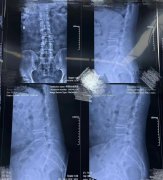

【冶金动态】陕西冶金医院成功开展OLIF腰椎微创椎体间融合术!

如果说传统开放性腰椎手术 走的是一条大刀阔斧的路 那么OLIF微创手术 则是走巧妙的创新之路 10月19日上午10时 陕西冶金医院神经脊柱科 成功实施OLIF腰椎微创椎体间融合术 标志着陕西